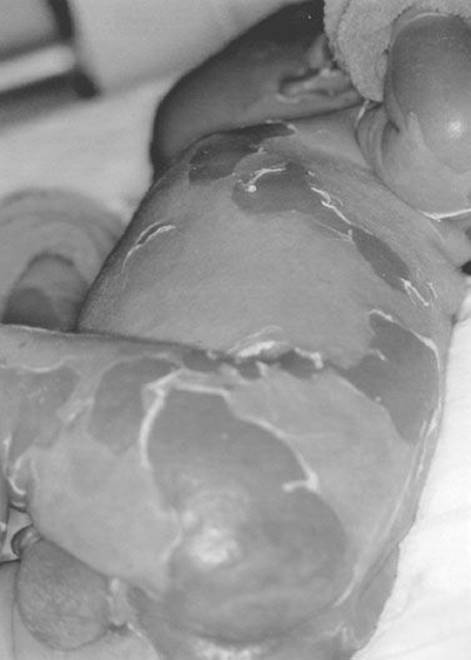

Staphylococcal scalded skin syndrome (SSSS) (Fig. 170.1) occurs in children and, rarely, adults and is caused by an exotoxin from an infecting strain of coagulase-positive Staphylococcus aureus. The disease may present as a prodrome of fever, irritability, malaise, and exquisite skin tenderness; in other cases, the child presents with the sudden onset of generalized erythema. The skin is red, warm, and very tender. Ill-defined, flaccid bullae then desquamate in large sheets. Gentle lateral stroking of the skin causes the epidermis to separate (Nikolsky sign).

FIGURE 170.1 Staphylococcal scalded skin syndrome. A 10-day-old Caucasian boy with staphylococcal scalded skin syndrome. He was treated with fluids, oral dicloxacillin, and wound care. His skin healed completely and without scarring within 2 weeks of this photograph being taken. (From Avery GB, Fletcher MA, MacDonald MG. Neonatology: Pathophysiology and Management of the Newborn. 5th ed. Philadelphia, PA: Lippincott Williams & Wilkins; 1999:1199, with permission.)